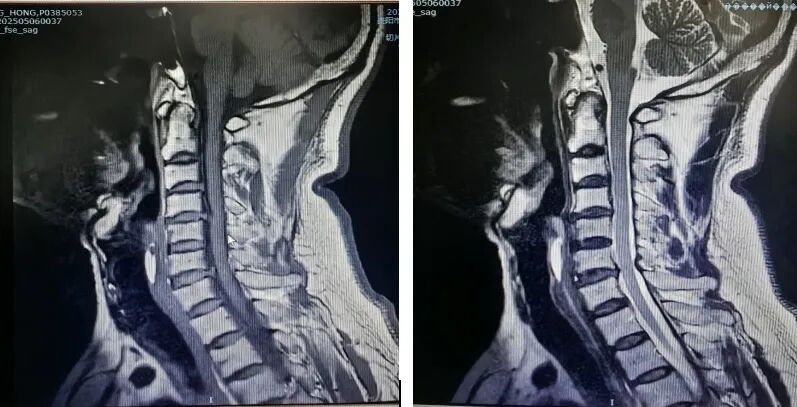

患者因"頭痛、雙上肢麻木伴下肢乏力1月"入院,此前長期保守治療效果不佳,癥狀持續(xù)加重并出現(xiàn)行走不穩(wěn)。經(jīng)多學科聯(lián)合會診,團隊決定采用國際先進的零切跡cage融合術。手術歷時2小時,出血量僅10ml,術后患者即刻感到頸部及肢體癥狀顯著緩解,術后三天即可下床活動,微創(chuàng)切口(3—4厘米)及快速康復效果獲家屬高度贊譽。

相較于傳統(tǒng)鋼板融合術,零切跡cage融合術實現(xiàn)了技術升級。

零切跡cage融合術:

1.采用小型化、低切跡的融合器(cage),切口僅3—4厘米,術中對軟組織剝離少,有效降低血管、神經(jīng)損傷風險;

2.其零切跡設計貼合頸椎生理曲度,減少對食管刺激,避免術后吞咽不適;

3.cage融合可促進骨組織自然生長,穩(wěn)定性佳,能更好地維持頸椎活動度,加速患者術后康復進程,縮短住院時間。